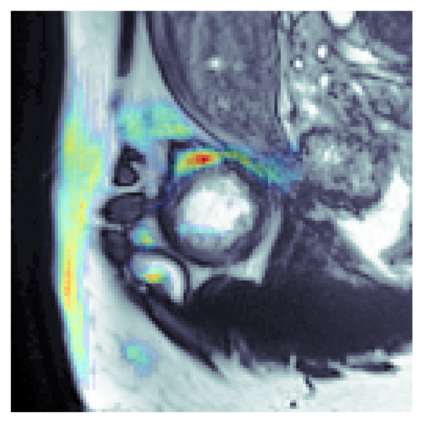

The sigmoid activation is the standard output activation function in binary classification and segmentation with neural networks. Still, there exist a variety of other potential output activation functions, which may lead to improved results in medical image segmentation. In this work, we consider how the asymptotic behavior of different output activation and loss functions affects the prediction probabilities and the corresponding segmentation errors. For cross entropy, we show that a faster rate of change of the activation function correlates with better predictions, while a slower rate of change can improve the calibration of probabilities. For dice loss, we found that the arctangent activation function is superior to the sigmoid function. Furthermore, we provide a test space for arbitrary output activation functions in the area of medical image segmentation. We tested seven activation functions in combination with three loss functions on four different medical image segmentation tasks to provide a classification of which function is best suited in this application scenario.